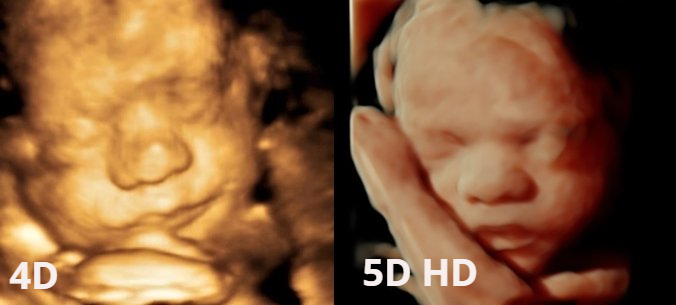

Imagen 8K ¿Qué es? La imagen 8K es una técnica novedosa que aporta mayor sensación de realismo a las imágenes que se obtienen mediante la adquisición de ecografía 5D que, ya de por sí, resulta ser una técnica ecográfica hiper-realista. Dicha técnica suaviza y texturiza las imágenes obtenidas, aumenta los contrastes y se incorporan detalles que aumentan, si cabe, la sensación de realismo. A petición del cliente la imagen seleccionada es procesada y entregada durante los días posteriores a la realización de la ecografía 5D. En Centre Miramed estamos orgullosos de poder poner a disposición de nuestros/as clientes/as la técnica 8K como ejemplo de vanguardia y crecimiento continuado.